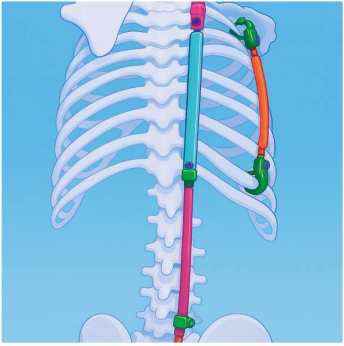

Tendência atual: técnicas menos invasivas e correção progressiva

Diante das altas taxas de complicações associadas às artrodeses extensas, especialmente em pacientes frágeis, houve nos últimos anos uma tendência ao desenvolvimento e à utilização de técnicas menos invasivas, aplicadas de forma mais precoce.

Uma dessas abordagens é a técnica bipolar descrita pelo professor Lofti Miladi, amplamente divulgada na literatura especializada. Essa técnica utiliza pontos de fixação proximais e distais, permitindo uma correção progressiva da deformidade, acompanhando o crescimento e a adaptação do corpo, com:

- menor agressão cirúrgica inicial;

- menor impacto sobre o crescimento;

- possibilidade de adiar cirurgias maiores.

Essa estratégia busca equilibrar controle da deformidade, preservação funcional e redução de riscos em pacientes com escoliose neuromuscular.